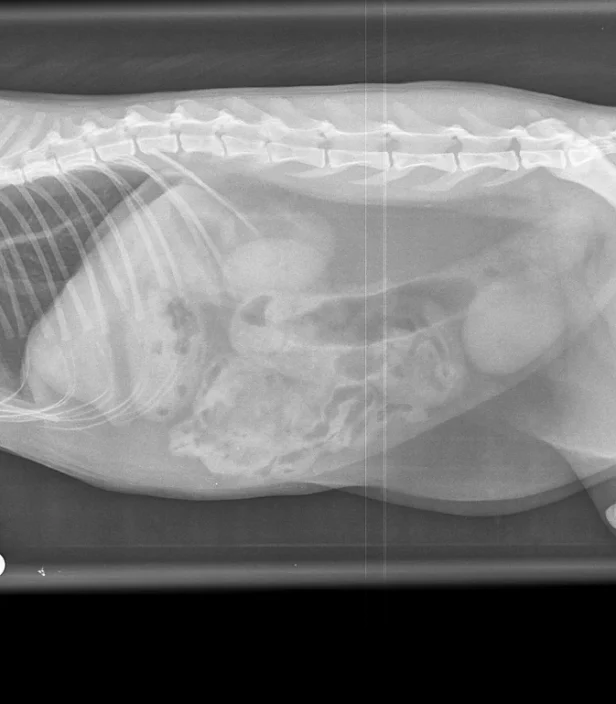

Most x-rays are carried out under sedation or general anaesthesia and allow us to assess the skeletal system and internal organs of your cat. Because the system is digital we can take multiple pictures without having to unduly extend the time your cat is asleep, and obtain high quality images suitable for interpretation in-house (including by our specialist surgeons) and for exporting digitally for second opinions. We are always happy to show you your cat’s x-rays and explain our findings.